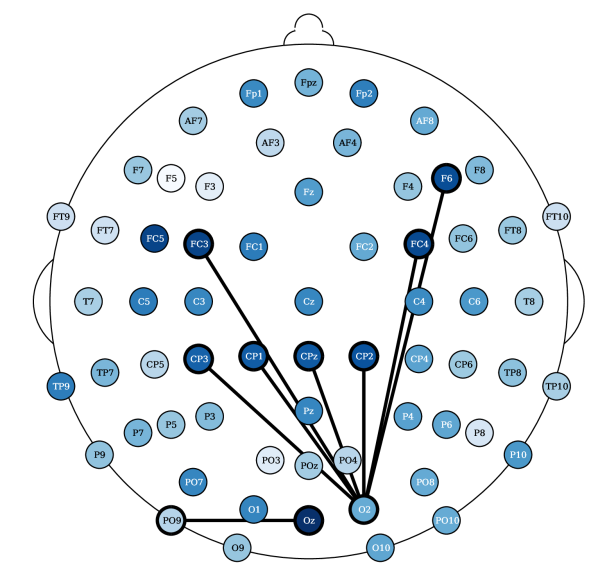

Most relevant electrode relations. Consider the relevance of the attention scores, computed from models (ii) and (iv), both having topographical attention at the EEG channel dimension, and model (iv) with projected random Fourier features in the latent space. These relevances were propagated, using the LRP algorithm [36] described in Appendix 0.E, through the attention style based posterior. Figure 5 shows the relevances plotted in a white to blue scale, from less relevant to most relevant, respectively. The latter only shows the edges that are above the percentile. The presence of an edge between electrodes suggests that either this connection yields a Markovian property for the EEG instance or, otherwise, it is relevant to add fMRI style conditioned on these connections (recall from Section 3.2 that posterior conditions the latent EEG representation such that ). For resting state fMRI, both Figures 10(a) and 5(a) show connections of parietal and occipital channels (O2 electrode in Figure 10(a) and Pz electrode in Figure 5(a)) with frontal and central channels to be the most relevant (above the 99.7 percentile of relevance). Figure 10(a) reports an additional connection between the Oz and PO9 electrodes, a correspondence between an occipital and a parietal-occipital electrode, which is in accordance with connectivity observations reported by Rojas et al. [6]. There were no reported relevances for the electrodes (T) placed in the temporal regions for resting state settings. In contrast, in task-based fMRI synthesis, relevant relationships between temporal (FT9 and TP9) and frontal/central (Fp2 and C1/C2, respectively) electrodes were reported, see Figures 10(b) and 5(b). In both of these figures, connections between central and parietal electrodes were observed. Particularly, there were reported connections between Cz with Pz and CP5 and CP2 electrodes in Figure 10(b). And connections between Pz and P8 with CPz electrodes in Figure 5(b).

Laboratory setup impacts EEG to fMRI synthesis. The results show that it is more difficult, according to the RMSE metric, to synthesize task-based fMRI than resting state. This observation is in contrast with studies that report that resting state fMRI is inherently more complex than task based fMRI [37]. The SSIM metric, in contrast to the RMSE, shows less significant differences for the Oddball recordings in favor of fMRI synthesis in the resting state. However, the CN-EPFL dataset is not in accordance with the latter. This performance heterogeneity across the datasets may not only rise from the characteristics of the recording sessions, but may also be also propelled by the different preprocessing techniques employed. Each dataset is publicly available and is supported with published studies, having unique equipment, experimental protocols, and algorithms. CN-EPFL dataset is the most complete one, with a total of 20 individuals and with a resolution of mm, which makes a total of voxels. These differences, caused by working with 3 Tesla (CN-EPFL dataset) versus 1.5 Tesla (NODDI and Oddball datasets) scanners, significantly impact the spatial resolution, which for the datasets NODDI and Oddball produce and voxels, respectively, with around mm voxel size. One has to further account for the original recording artifacts and disruptions caused by the applied preprocessing techniques. For instance, Oddball dataset contains intra and inter individual wise misalignments across fMRI volumes. This may be the cause of poorer performance of all methods when compared to the other datasets. In addition, Oddball relies on a different EEG electrode positioning system, having a total of electodes that were not placed in accordance with the 10-20 system [26]. Although NODDI and CN-EPFL recordings are in accordance with this system, each selected unique electrode locations (see the different electrode placements between Figures 5(a) and 5(b)). Finally, the different EEG sampling frequencies, with Hz, Hz and Hz considered in NODDI, Oddball and CN-EPFL recordings, respectively, further affect architectural operations and subsequently impact the learning.